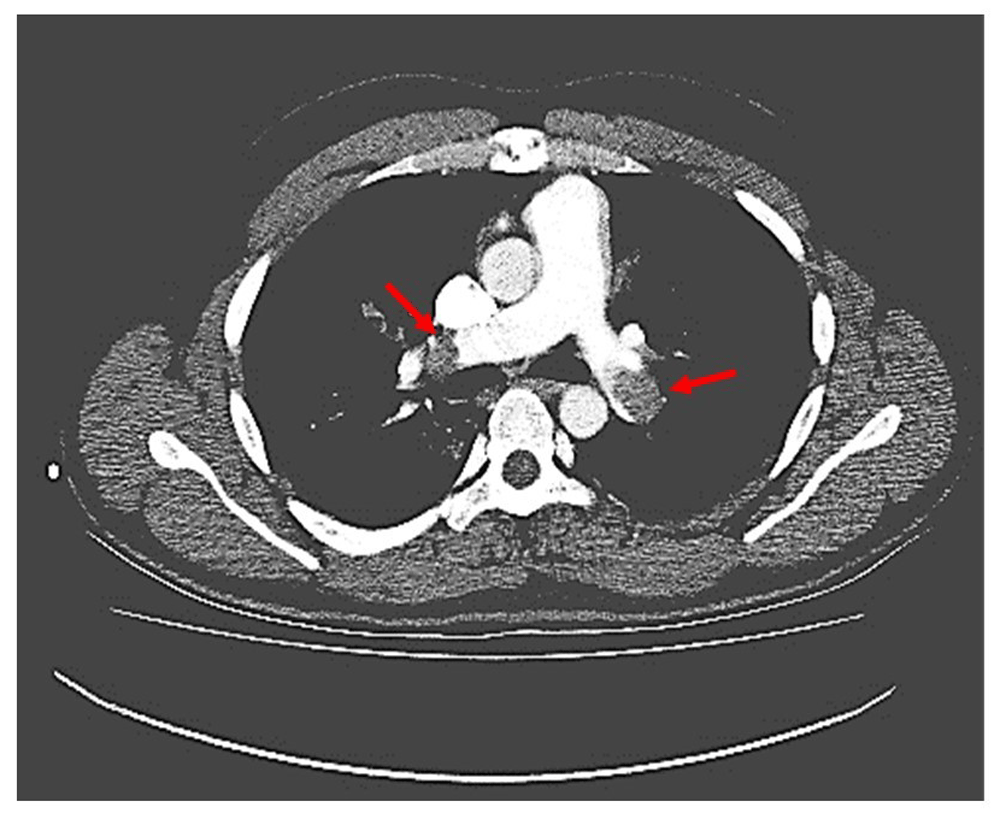

CT-Pulmonary Angiogram (Figure 1) was suggestive of a massive pulmonary thromboembolism. The pulmonary trunk was dilated to ~30 mm. There was a non-lumen occluding circumferential filling defect in the main pulmonary trunk, with maximum thickness of 4.5 mm. A large partial-lumen occluding filling defect was noted in the left main pulmonary artery, which was extending further into the hilar branch, occluding the lumen completely. Another larger complete lumen occluding filling defect was noted in the right main pulmonary artery. These filling defects were extending into the segmental and sub-segmental branches of the lateral segment of the right middle, lingual and bilateral lower lobe. The RV: LV ratio was 2:1. All four pulmonary veins were normal, and there was no evidence of mediastinal pathology.